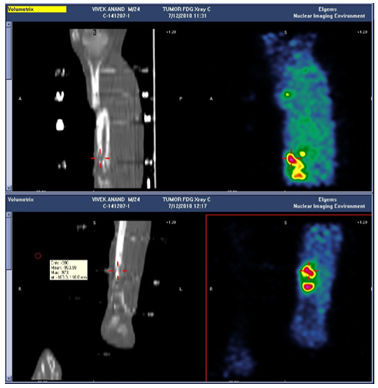

| PET Scan | ||

| The FDG PET Scan showing active infection at the lower fracture site. An arterial DSA (Digital Subtraction Angiogram) was done to determine the course and patency of the arteries. | ||